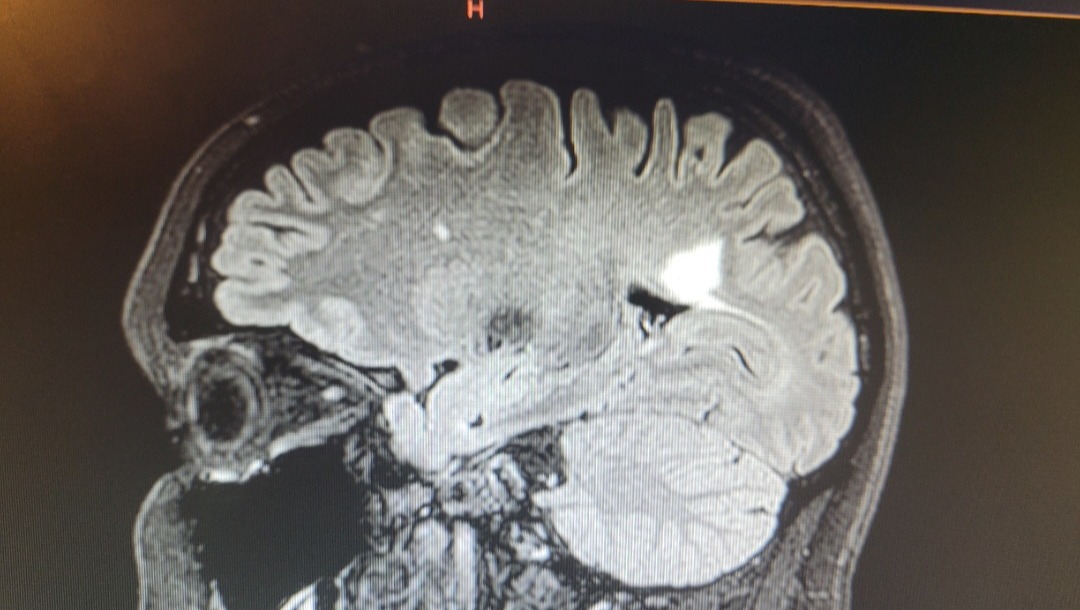

A few days later after 2 MRI scans I was told this was an MS attack and I had multiple lesions on my brain which caused irreversible damage.

Since being diagnosed in 2021 I've never really gone into "remission" having bouts of attacks and new areas of inflammation on my brain and spine every few months. Subsequently, being diagnosed with rapidly evolving severe MS.